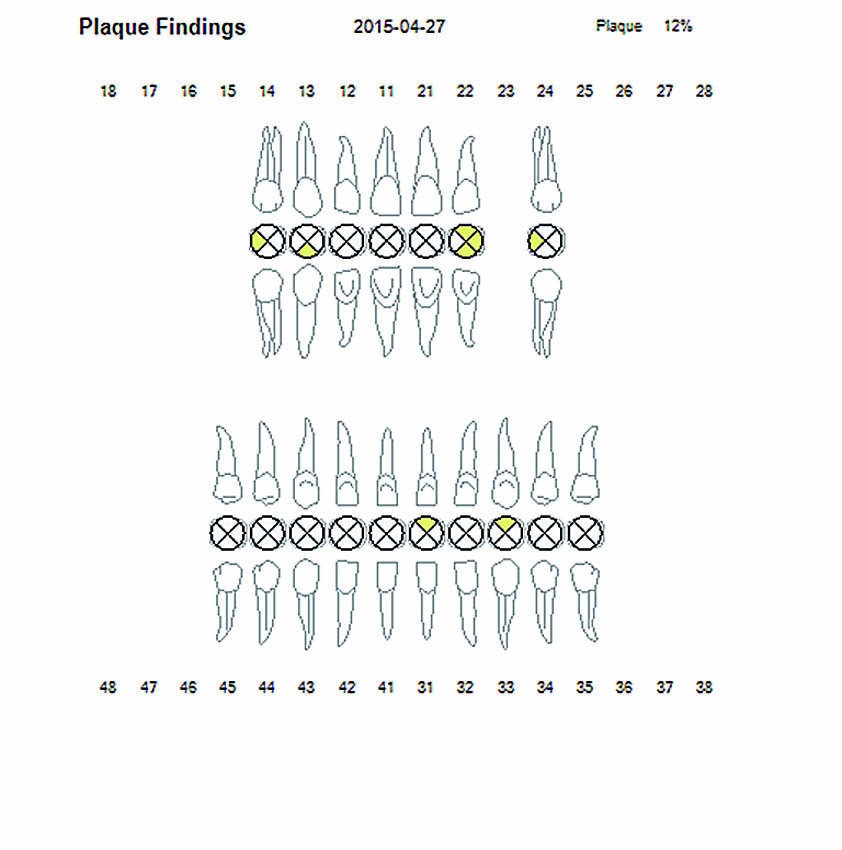

Η λεπτομερής κλινική εξέταση θα περιελάμβανε, μεταξύ των άλλων, στοιχεία σχετικά με το βάθος των περιοδοντικών θυλάκων (ΒΘ), την αιμορραγία κατά την ανίχνευση (ΑΚΑ) και τον δείκτη πλάκας (ΔΠ).

Πριν τη θεραπεία, η ασθενής υποβλήθηκε σε διαδικασία υποουλικού καθαρισμού με ξέστρα υπερήχων. Μετά τον καθαρισμό, η κλινική κατάσταση της ασθενούς βελτιώθηκε. Στη συνέχεια, εφαρμόστηκε ένα laser Nd:YAG για την αποστείρωση και την απολύμανση των περιοδοντικών θυλάκων (Εικ. 3 έως 7) και laser Er:YAG για την απομάκρυνση της υποουλικής τρυγίας (Εικ. 8 έως 12).